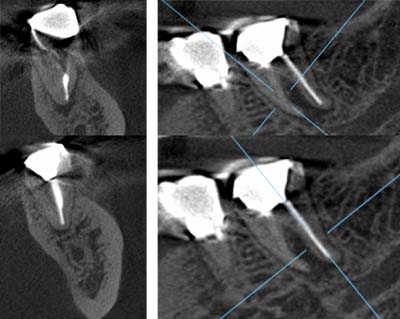

当院での治療例です。ご来院された(初診時)治療前の状態と根充後(治療後)の状態をレントゲンとCTで確認すると次のようになります。

しっかりと根充されていることがCTにより確認すことができます。